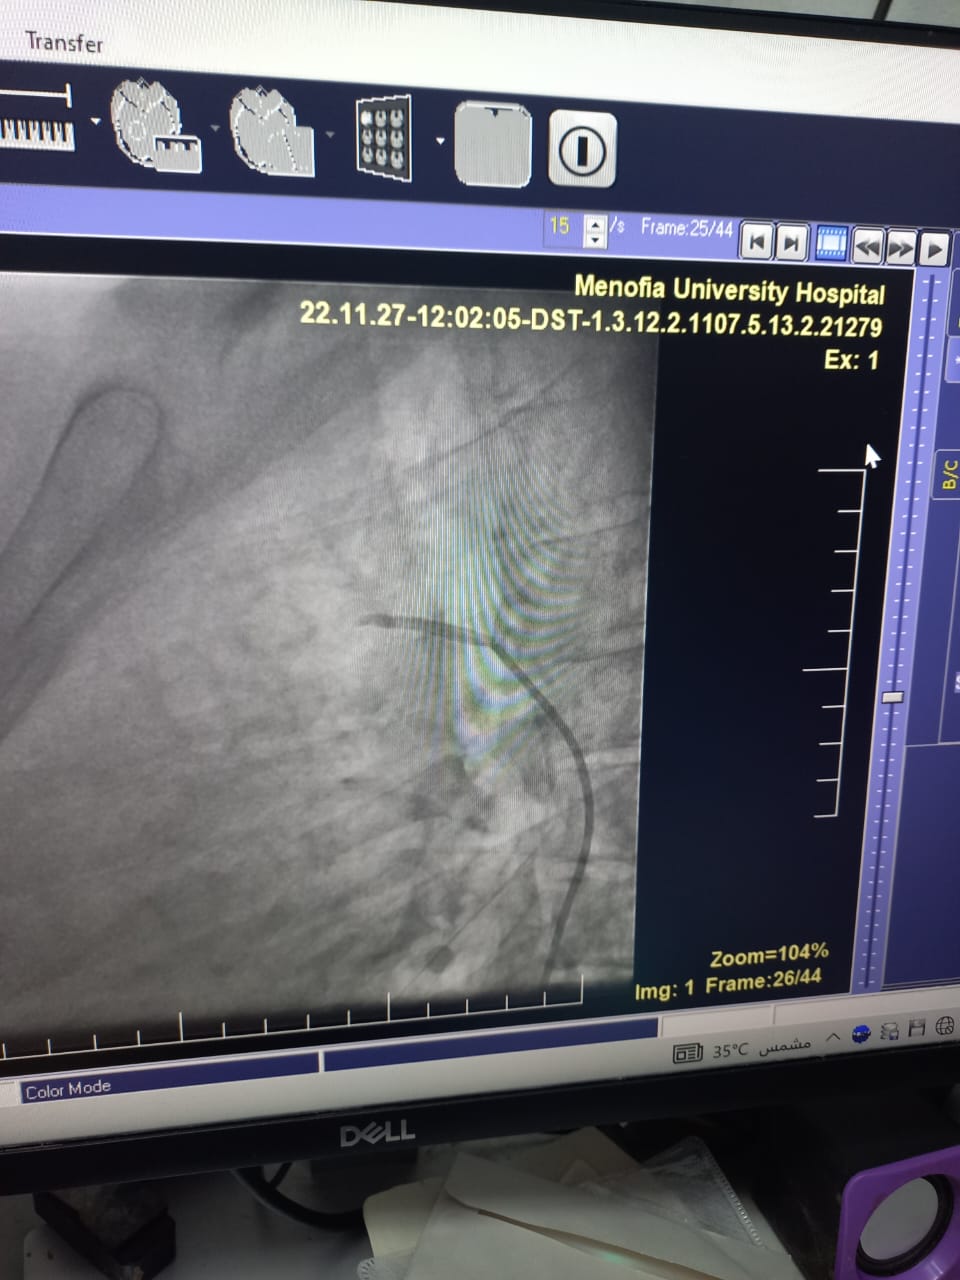

من جانبه أوضح الدكتور محمد النعمانى رئيس قسم القلب و الأوعية الدموية أنه تم عمل غلق وصلة شريانية بين الشريان الرئوي والأورطى لطالبة بإحدى كليات جامعة المنوفية عن طريق القسطرة الداخلية بدلا من جراحة القلب المفتوح والتى تجرى عن طريق تخدير موضعى فقط والمريض واعى ويخرج المريض من المستشفى في اليوم التالى للقسطرة مباشرة. و أضاف النعماني أنها تعد حالة من الحالات الصعبة نظرا لكون الوصلة الشريانية طويلة و يبلغ طولها حوالى ٢٧ مم.